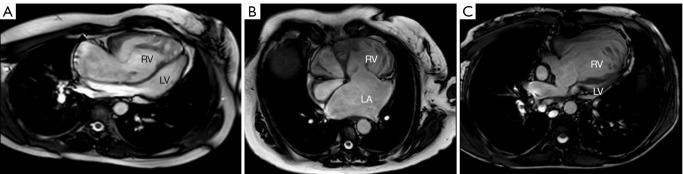

Methods: This retrospective single-center cohort study included 21 adult patients with sRV and signs of heart failure [6 with d-transposition of the great arteries (d-TGA) post-atrial switch, 7 with congenitally corrected transposition of the great arteries (cc-TGA), and 8 with univentricular right heart in Fontan circulation]. Changes in functional New York Heart Association (NYHA) class, N-terminal pro-B-type natriuretic peptide (NT-proBNP) levels, sRV function, and renal function were assessed before and after initiating or escalating heart failure pharmacotherapy with ARNi and/or SGLT2i. The median follow-up was 15 months (1.24 years).